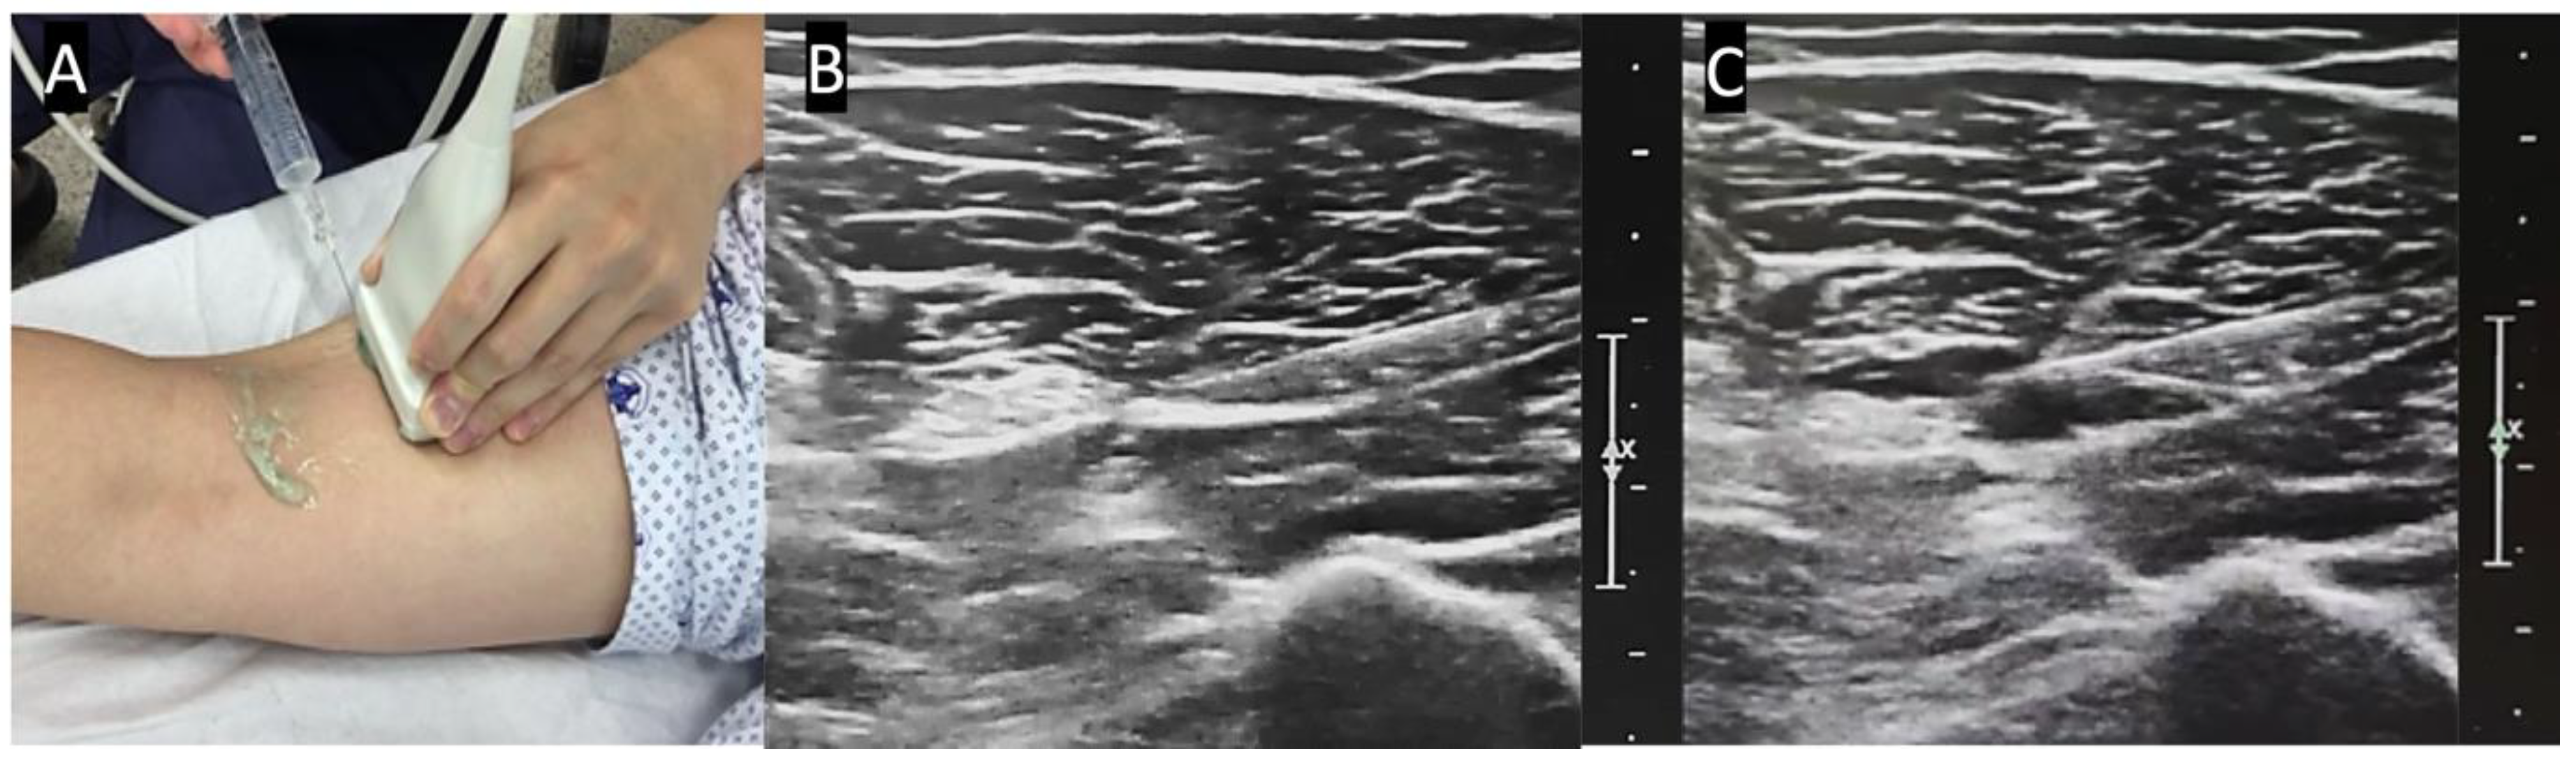

2.2. Anesthetic Method and Technique